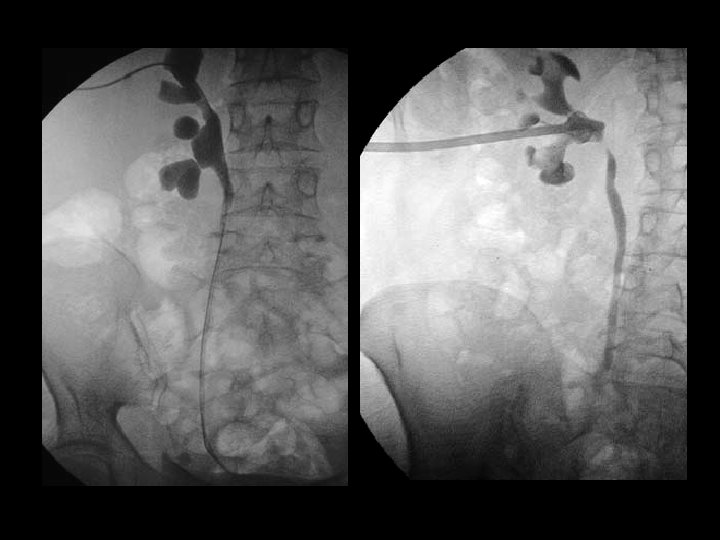

Perkütan Antegrad NEFROSTOMİ